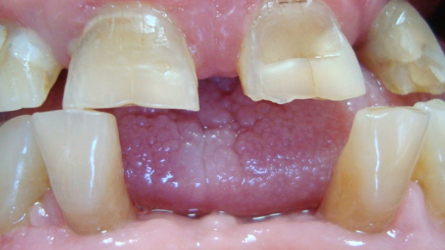

Clinically, gingival enlargement is presented as painless, firm, nodular expansion of interdental papilla. It is a generalised condition, but is more severe in the maxillary and mandibular anterior segments. Gingival enlargement occurs in proximity to the teeth and not in toothless jaw sections. Drug-induced gingival overgrowth can occur in sites with minimal or no plaque, but it interferes with oral hygiene and may often lead to chronic inflammation, which complicates the enlargement. In cases with secondary gingival inflammation, the gingiva is bluish-red in colour, with a lobulated surface and a tendency for bleeding.(7)

Two patients aged 67 and 73 with complaints of gingival enlargement were referred to the department of Periodontology, Medical University, Plovdiv. Besides gingival hyperplasia, they reported also bleeding gums, halitosis and inability for good oral hygiene. The patients’ medical history revealed systemic use of ACE inhibitors (Prestarium 2.5 mg and Co-Enalapril 20mg/12.5mg) for antihypertensive treatment.

The intraoral examination revealed generalised, grade II gingival enlargement(20) in the anterior segment of the mandible (case I and case II) and the maxilla (case II). There was a high score of debris and calculus index according to Greene-Vermillion index.(21) The gingiva showed signs of inflammation as redness, bleeding on probing and suppuration. Halitosis was also detected. The measurement of pocket probing depth revealed deep pockets of about 7-8 mm (Figs. 2-14).